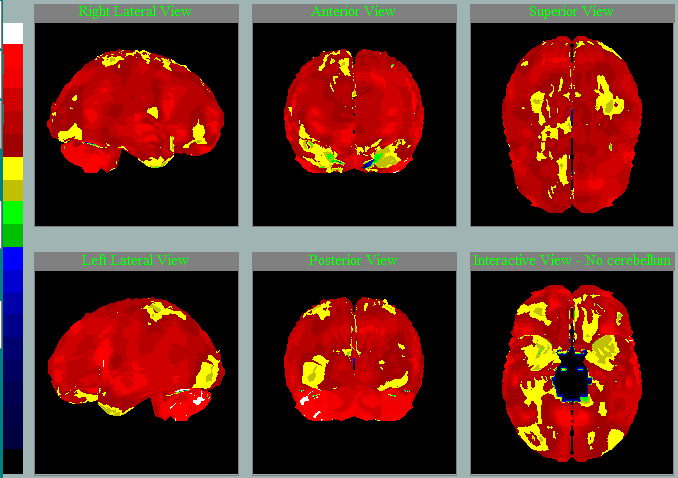

Oproti jiným pomocným metodám SPECT mozku je levný, prakticky neinvazivní a snadno dostupný v každé větší nemocnici. Vyšetření se dá zpracovat do trojrozměrného mozku pomocí speciálního programu NeuroGam. Tato metodika přináší důležité informace týkající se prostorového zhodnocení korové perfúze. Hypoperfúzní oblasti jsou jasně barevně odlišeny od normálního prokrvení, protože se výsledek porovnává s dostupnou normálovou populací. Perfúzní vzorce mohou v některých případech významně napomáhat správné diagnostice, a to lépe než strukturální CT / MR mozku, kde je vidět úbytek tkáně až později. O klinickém přínosu SPECT mozku je možné se dozvědět ve 14minutové přednášce.

Takto na SPECT mozku zpracovaném NeuroGamem vypadá:

Perfúze při neurodegenerativním onemocnění mozku